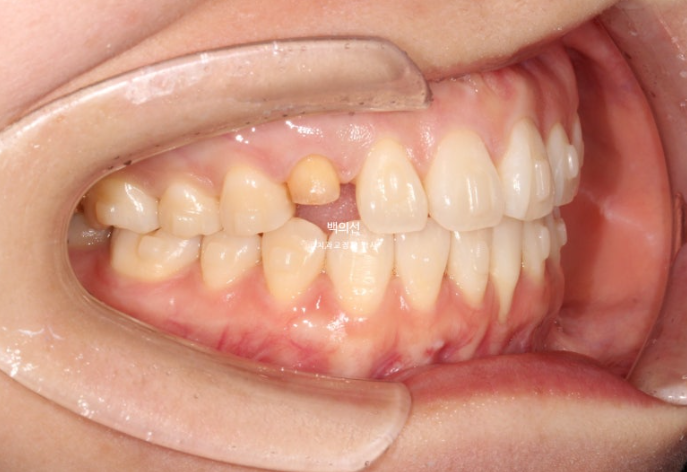

잔존유치는 영구치 송곳니가 매복되는 바람에 남아있는 상태입니다.

그런데 잔존유치에 교정력을 가할경우, 안그래도 약한 유치 뿌리가 녹을 수 있어서 잔존유치는 치료기간 내내 치아이동 없이 위치 잠금으로 계획해야 하고 어태치먼트조차 붙이지 않는 게 좋습니다.

색이 어두운 치아는 잔존유치에 레진을 덮어놓은 상태이고 이번기회에 재교정을 하면서 이 치아도 변색된 레진을 제거하고 라미네이트든 크라운이든 깔끔하게 치료를 원하셨습니다.

아래 앞니 뿐만 아니라 파란화살표 앞니도 뿌리가 앞으로 나가있습니다. 아직 아래앞니처럼 잇몸퇴축이 일어나지는 않았지만, 튀어나간 뿌리를 입천장쪽으로 데려오는 치료를 해야 잇몸이 내려가는걸 예방할 수 있습니다.

위 앞니가 한쪽으로 기울어져 있는데다가 한쪽 송곳니가 안보이니 앞니 교합평면 기울어짐이 심해보입니다. 캔팅이라고 하죠.